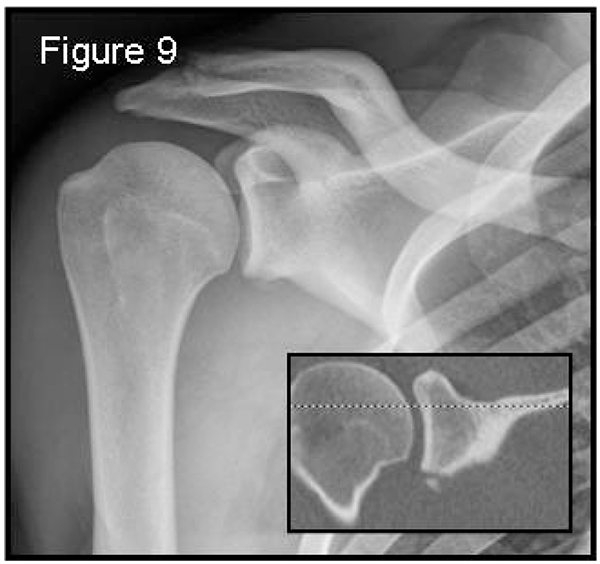

Fig. (9) Grashey view: a true antero-posterior X-ray view in the scapular plane. 55x51mm (150 x 150 DPI).